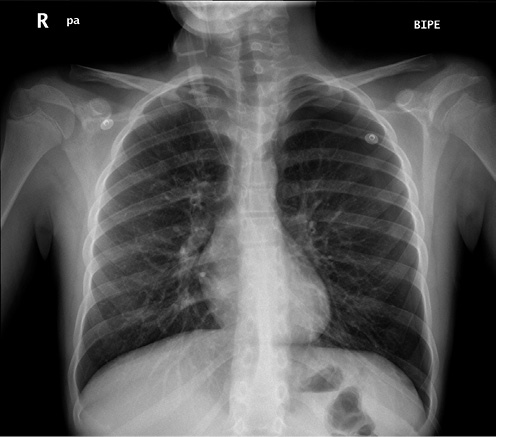

Anamnesis Lactante de 9 meses, correctamente vacunado para su edad, sin antecedentes patológicos relevantes, que acude a urgencias por un cuadro clínico de: fiebre de hasta 39ºC, irritabilidad, rechazo de las tomas y quejido intermitente de 3 días de evolución, con empeoramiento en las últimas 24 horas. Tos y rinorrea sin otra sintomatología acompañante. Exploración física SatO2: 94%. FC: 135 lpm. Aceptable estado general, algo decaído. Reactivo. Bien nutrido, hidratado y perfundido. Relleno capilar inmediato. No lesiones en piel. Buena perfusión periférica. Quejido respiratorio, tiraje inter y subcostal leve, con hipoventilación en hemitórax derecho a la auscultación pulmonar. Auscultación cardíaca rítmica y sin soplos. Sin otros hallazgos patológicos. Pruebas complementarias – Laboratorio: destaca leucocitosis (21.400/μl, neutrófilos 19.300 μl) y elevación de reactantes de fase aguda (proteína C reactiva. 29,5 mg/dl; procalcitonina 18,53 ng/ml). – Radiografía de tórax (Fig. 5).

Figura 5. Radiografía de tórax